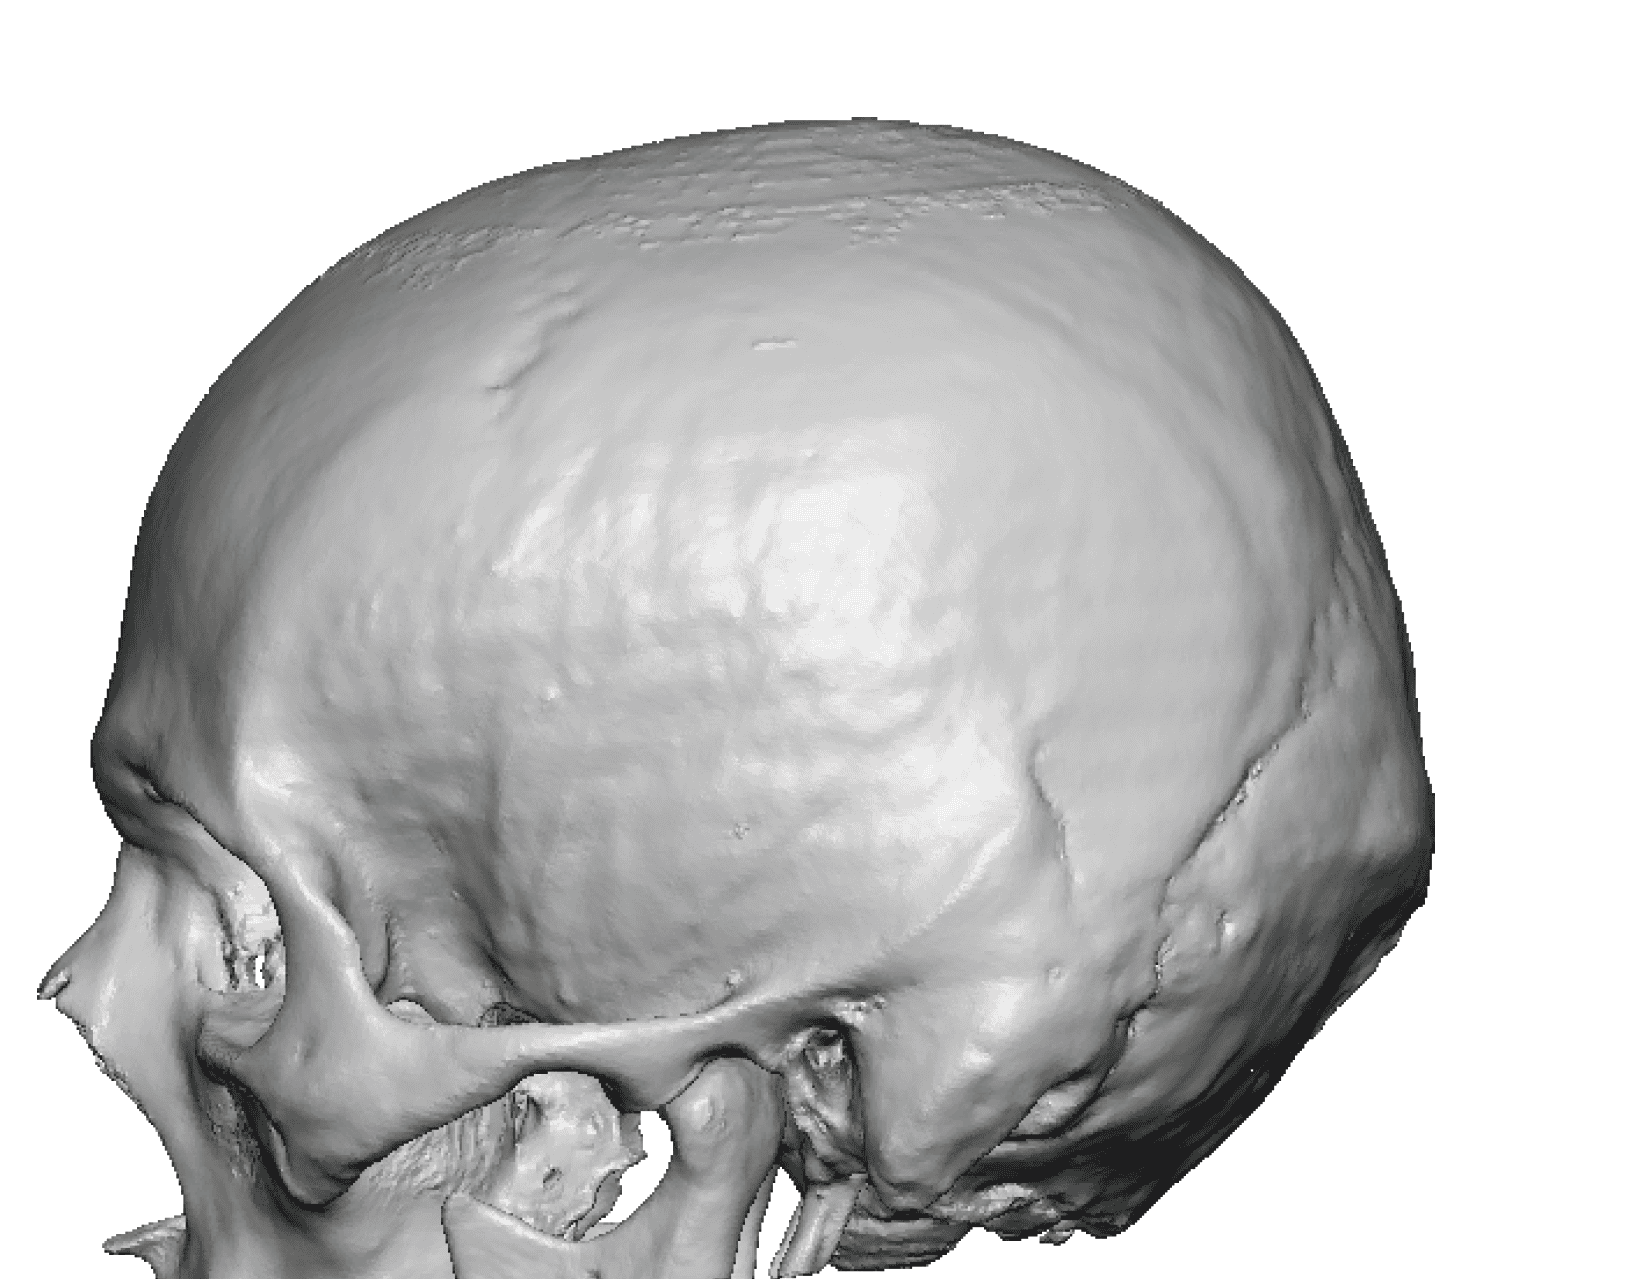

Severe narrowing skull deformity from prior sagittal craniosynostosis repair as an adult.

Complete replacement of entire skull by a custom implant with temporal fat injections.

Severe narrowing skull deformity from prior sagittal craniosynostosis repair as an adult.

Complete replacement of entire skull by a custom implant with temporal fat injections.